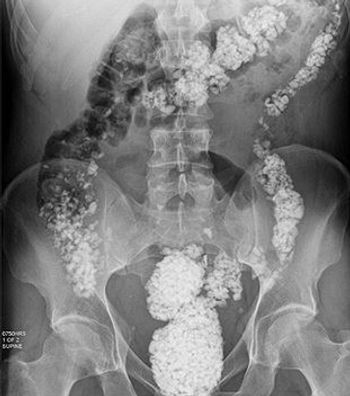

A homeless man with lithophagia; hereditary trichoepithelioma; IBD mimics: can you answer this week's quiz questions about these and 2 other disorders?